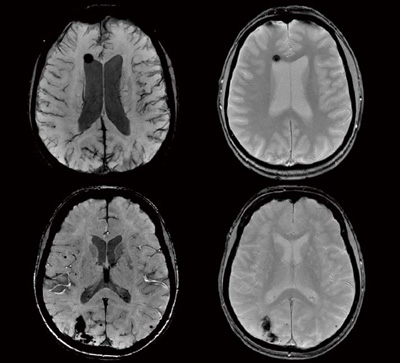

専用出品!mri〜様 □当クリニックの放射線科 - あぜみち脳神経クリニックの詳細情報

□当クリニックの放射線科 - あぜみち脳神経クリニック。4535-670-61683 - Philips - MRI - 8 Channel Sense Knee Coil。放射線科 | 浅草寺病院 | Sensoji Hospital。Signa HDxtのNewアプリケーションと標準化の取り組み-技術解説。緑と黒のドレスを着た女性のポートレート